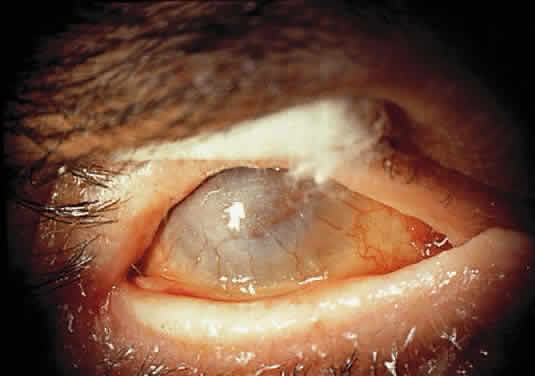

OCULAR FINDINGS. One of the few truly diagnostic and pathognomonic physical signs in clinical medicine is a Kayser-Fleischer corneal pigment ring found in patients with Wilson's disease (Fig. 5).This ring is recognized as a golden-brown, ruby-red, or green band of 1.0 to 3.0 mm, starting at the limbus but at the level of Descemet's membrane.53 The color of the ring is presumably caused by scattering and reflection of incident light and by photointerference effects created by the layers of copper granules. Such variables as size, shape, and unit density of the granules may account for the different appearances of the Kayser-Fleischer ring. The course of the Kayser-Fleischer ring has been well documented.54,55 The site of earliest pigment deposition is an arc in the superior periphery of the cornea from the 10- to 2-o'clock meridian. The arc spreads slowly toward the horizontal plane and gradually broadens. Later in the progression of the ring formation, a band appears inferiorly as a crescent stretching from the 5- to 7-o'clock positions. In time, the two arcs meet. With treatment, the sequence of events is reversed, and after the copper has reabsorbed, a pitted or beaten silver pattern may become apparent at the previous site of the ring. This is an indication that treatment has produced a negative copper balance.49 Decreased visual acuity is not a problem. Rarely, copper is deposited in the crystalline lens, giving an anterior subcapsular “sunflower” cataract.